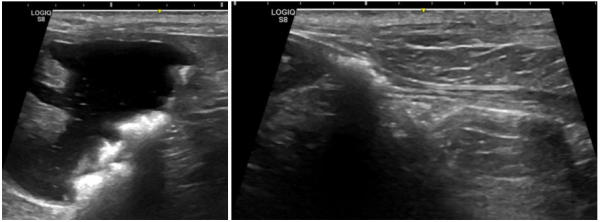

특히 복부 초음파는 방광결석의 위치·움직임·크기·요도 폐색 여부를

가장 정확하게 파악할 수 있어 필수적인 과정입니다.

까미는 방광, 요도, 신장에 결석이 있는 상태로 진단되었습니다.

다행히도 요도 결석이 요도 완전폐색을 유발하지 않은 상태라

응급 수술을 요하지는 않았습니다.